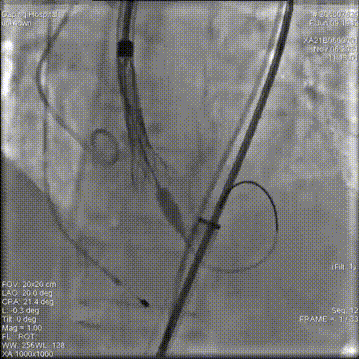

主动脉根部造影

18mm球囊预扩

第一次释放,位置过高回收定位

第二次释放,位置过低再回收释放

第三次瓣膜释放定位

23mm瓣膜释放中

20mm球囊后扩前造影

术后造影